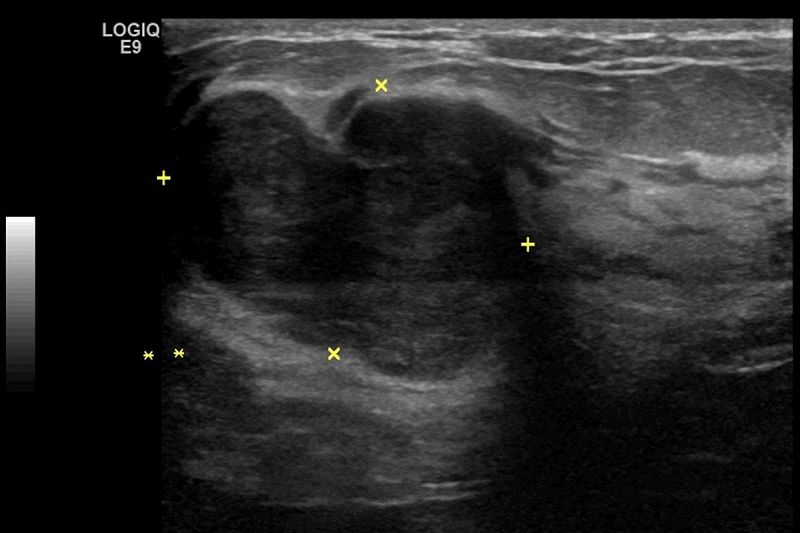

「這個腫塊會不會是癌症?」是許多病人最關心的問題,陳昱天醫師指出,判斷乳房腫瘤是否惡性,必須透過影像檢查與病理切片,層層檢驗,才能作出正確診斷與治療建議。乳房超音波與乳房攝影是腫瘤評估的主要影像工具,各有其適用族群與優勢。乳房超音波特別適用於年輕女性,因其乳腺較緻密,可清楚區分腫塊是液體囊腫還是實質腫瘤,並觀察腫瘤的邊界、形狀與血流分布,協助判斷良惡性。相較之下,乳房攝影則較適合40歲以上女性作為常規篩檢工具,能有效偵測微小的鈣化點與結構異常,對早期乳癌的發現具有高度敏感性。此外,若腫瘤具可疑特徵,則會安排粗針切片或真空輔助切片,進行病理檢查以作判別,部分高風險族群或術前需更精準評估者,也可透過核磁造影檢查協助釐清。